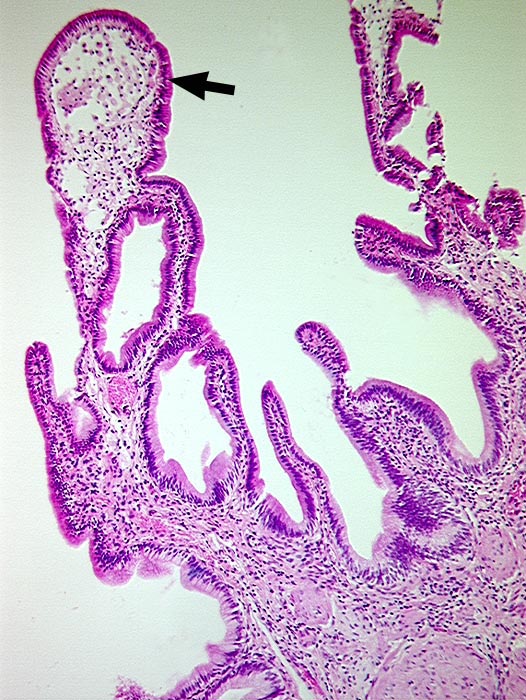

PathoPic ID 479 - Cholesteatose (Cholesterolose)

Cholesteatose (Cholesterolose)

Gallenblase

Durch Ansammlung von Schaumzellen leicht

►

aufgetriebene Zottenspitze.